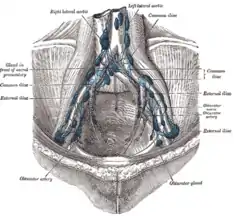

The most common sites for bladder cancer metastases are the lymph nodes, bones, lung, liver, and peritoneum.[78] The most common sentinel lymph nodes draining bladder cancer are obturator and internal iliac lymph nodes. The location of lymphatic spread depends on the location of the tumors. Tumors on the superolateral bladder wall spread to external iliac lymph nodes. Tumors on the neck, anterior wall and fundus spread commonly to the internal iliac lymph nodes.[79] From the regional lymph nodes (i.e. obturator, internal and external lymph nodes) the cancer spreads to distant sites like the common iliac lymph nodes and paraaortic lymph nodes.[80] Skipped lymph node lesions are not seen in bladder cancer.[79]